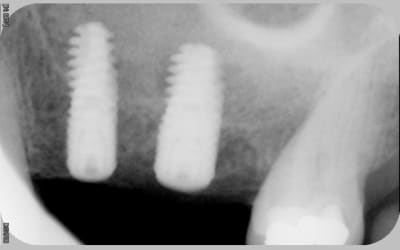

tous mes implants sont ostéo-intégrés, mais je trouve que la cratérisation est très importante et surtout très rapide.

donc pour moi, il y a un problème même si le taux de succès est de 100% en 2 ans.

voici les radios le jour de la pose

le krestal doit être en crestal et non en infra-osseux: il s'agit d'une connectique à plat et non d'un cône morse.

Je reviens là dessus car çà me semble être la clef

il me semble que sur le 1° cas présenté,la partie biseautée de l'implant est enfouie et que la cratérisation est nulle, idem pour l'implant mésial du dernier cas.

Sur son site Tekka préconise de mettre la partie supérieur de l'implant en juxtacrestal , donc le biseau est infraosseux...

J'avais rencontré le même pb sur un cas que j'avais présenté sur ce forum sur des IDcam et l'on m'avait fait remarqué à raison que l'enfouissement de l'implant distal était insuffisant, résultat a 6 mois cratérisation mésial et distal du dernier implant et à un an stabilisation .

Tu remarqueras que le biseau mésial de l'implant mésial qui a été correctement enfoui n'a pas bronché.